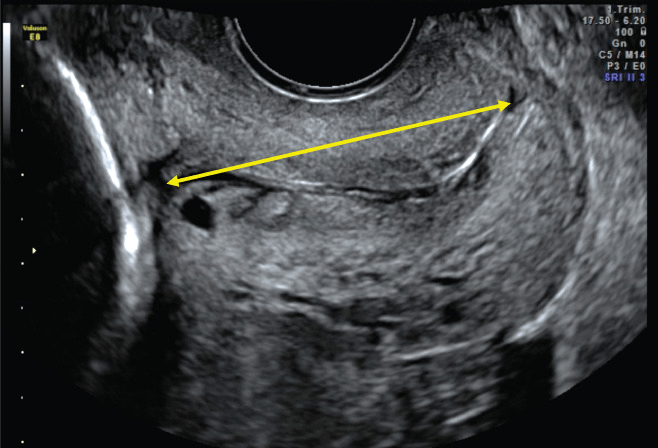

Cervix

The average length of the cervix is 3.5 cm. The cutoff usually used is 2.5 cm. If there is any cervical shortening or funneling (amniotic membranes bulging into the cervix) you may obtain a transvaginal ultrasound to confirm.

Potential pitfalls for transabominal approach:

Overfilled bladder masking cervical incompetence, also an underfilled bladder might make the cervix hard to image.